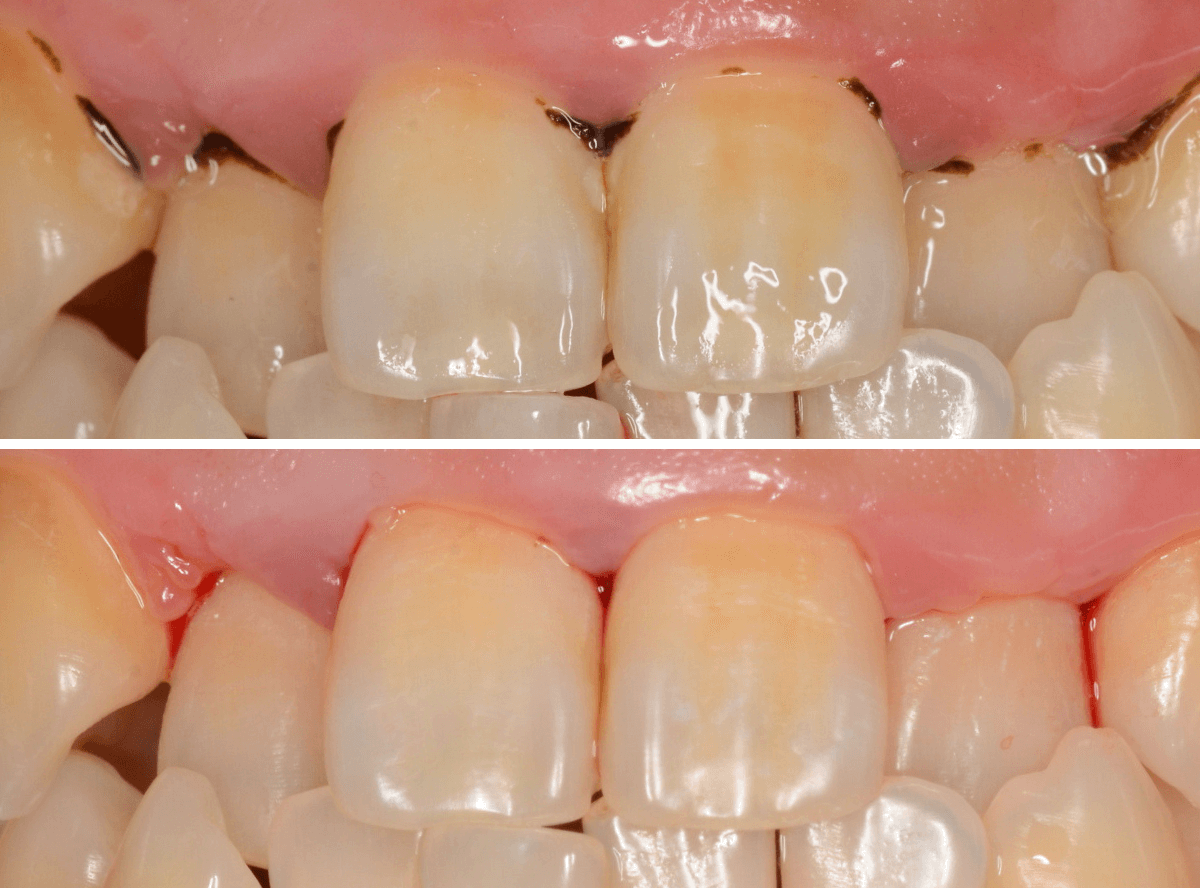

Case.1

「口臭が気になる」という理由で来院された患者さんです。

何度か来院され、歯石除去や歯ブラシ指導をしているのですが、まだまだ、徹底されていないのがわかります、もう少し頑張ってほしい(><)

歯肉の縁が赤く腫れています。こういった歯肉の中には歯石がたまっている可能性が大です。

この歯肉の中の見えない歯石は、歯肉の上の歯石よりも、歯周病の原因になります。

歯周病は痛みなどの自覚症状に乏しく、気づけば完全に治らない状態まで進んでいる事も多いので早期発見・治療が大切です。

保険診療では、歯石除去は一日で治療できる範囲が限られています。

今回は、上の前歯の部分の歯肉の中の歯石除去をしました。

歯石除去後です。

この状態を長く維持してもらう必要があります。

ここまで歯石除去の解説をしましたが、実は歯周病の治療で一番効果のある治療は、患者さんの日々の歯ブラシです。

せっかく歯石除去をしていても、歯ブラシがしっかりできていないと、効果は薄く、元の木阿弥になってしまいます。

患者さんには、今一度、気を引き締めて歯ブラシをしていただくよう指導しました。

どのくらい歯肉が治っていくのか経過観察する必要があります。